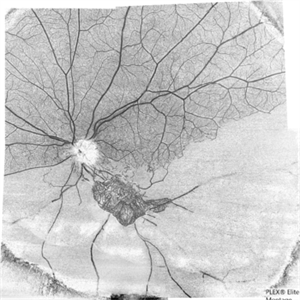

The Barren Field

A 59-year-old man with DM for 18 years operated for mature cataract. Post op left eye had a visual acuity of 20/80. Wide field swept source OCTA revealed gross vessel wipe out in inferior hemi quadrant with branching out neovascular frond inferior to disc with terminal loops, The patient underwent Anti VEGF injection followed by OCTA guided sectoral retinal photocoagulation.Image J software used here to generate reverse image that sharply delineates the non perfusion area.

Photographer: Sandeep Kumar

Imaging device: Optical coherence tomography system Zeiss Plex Elite 9000

Condition/keywords: hemi CRVO, neovascularization elsewhere (NVE)